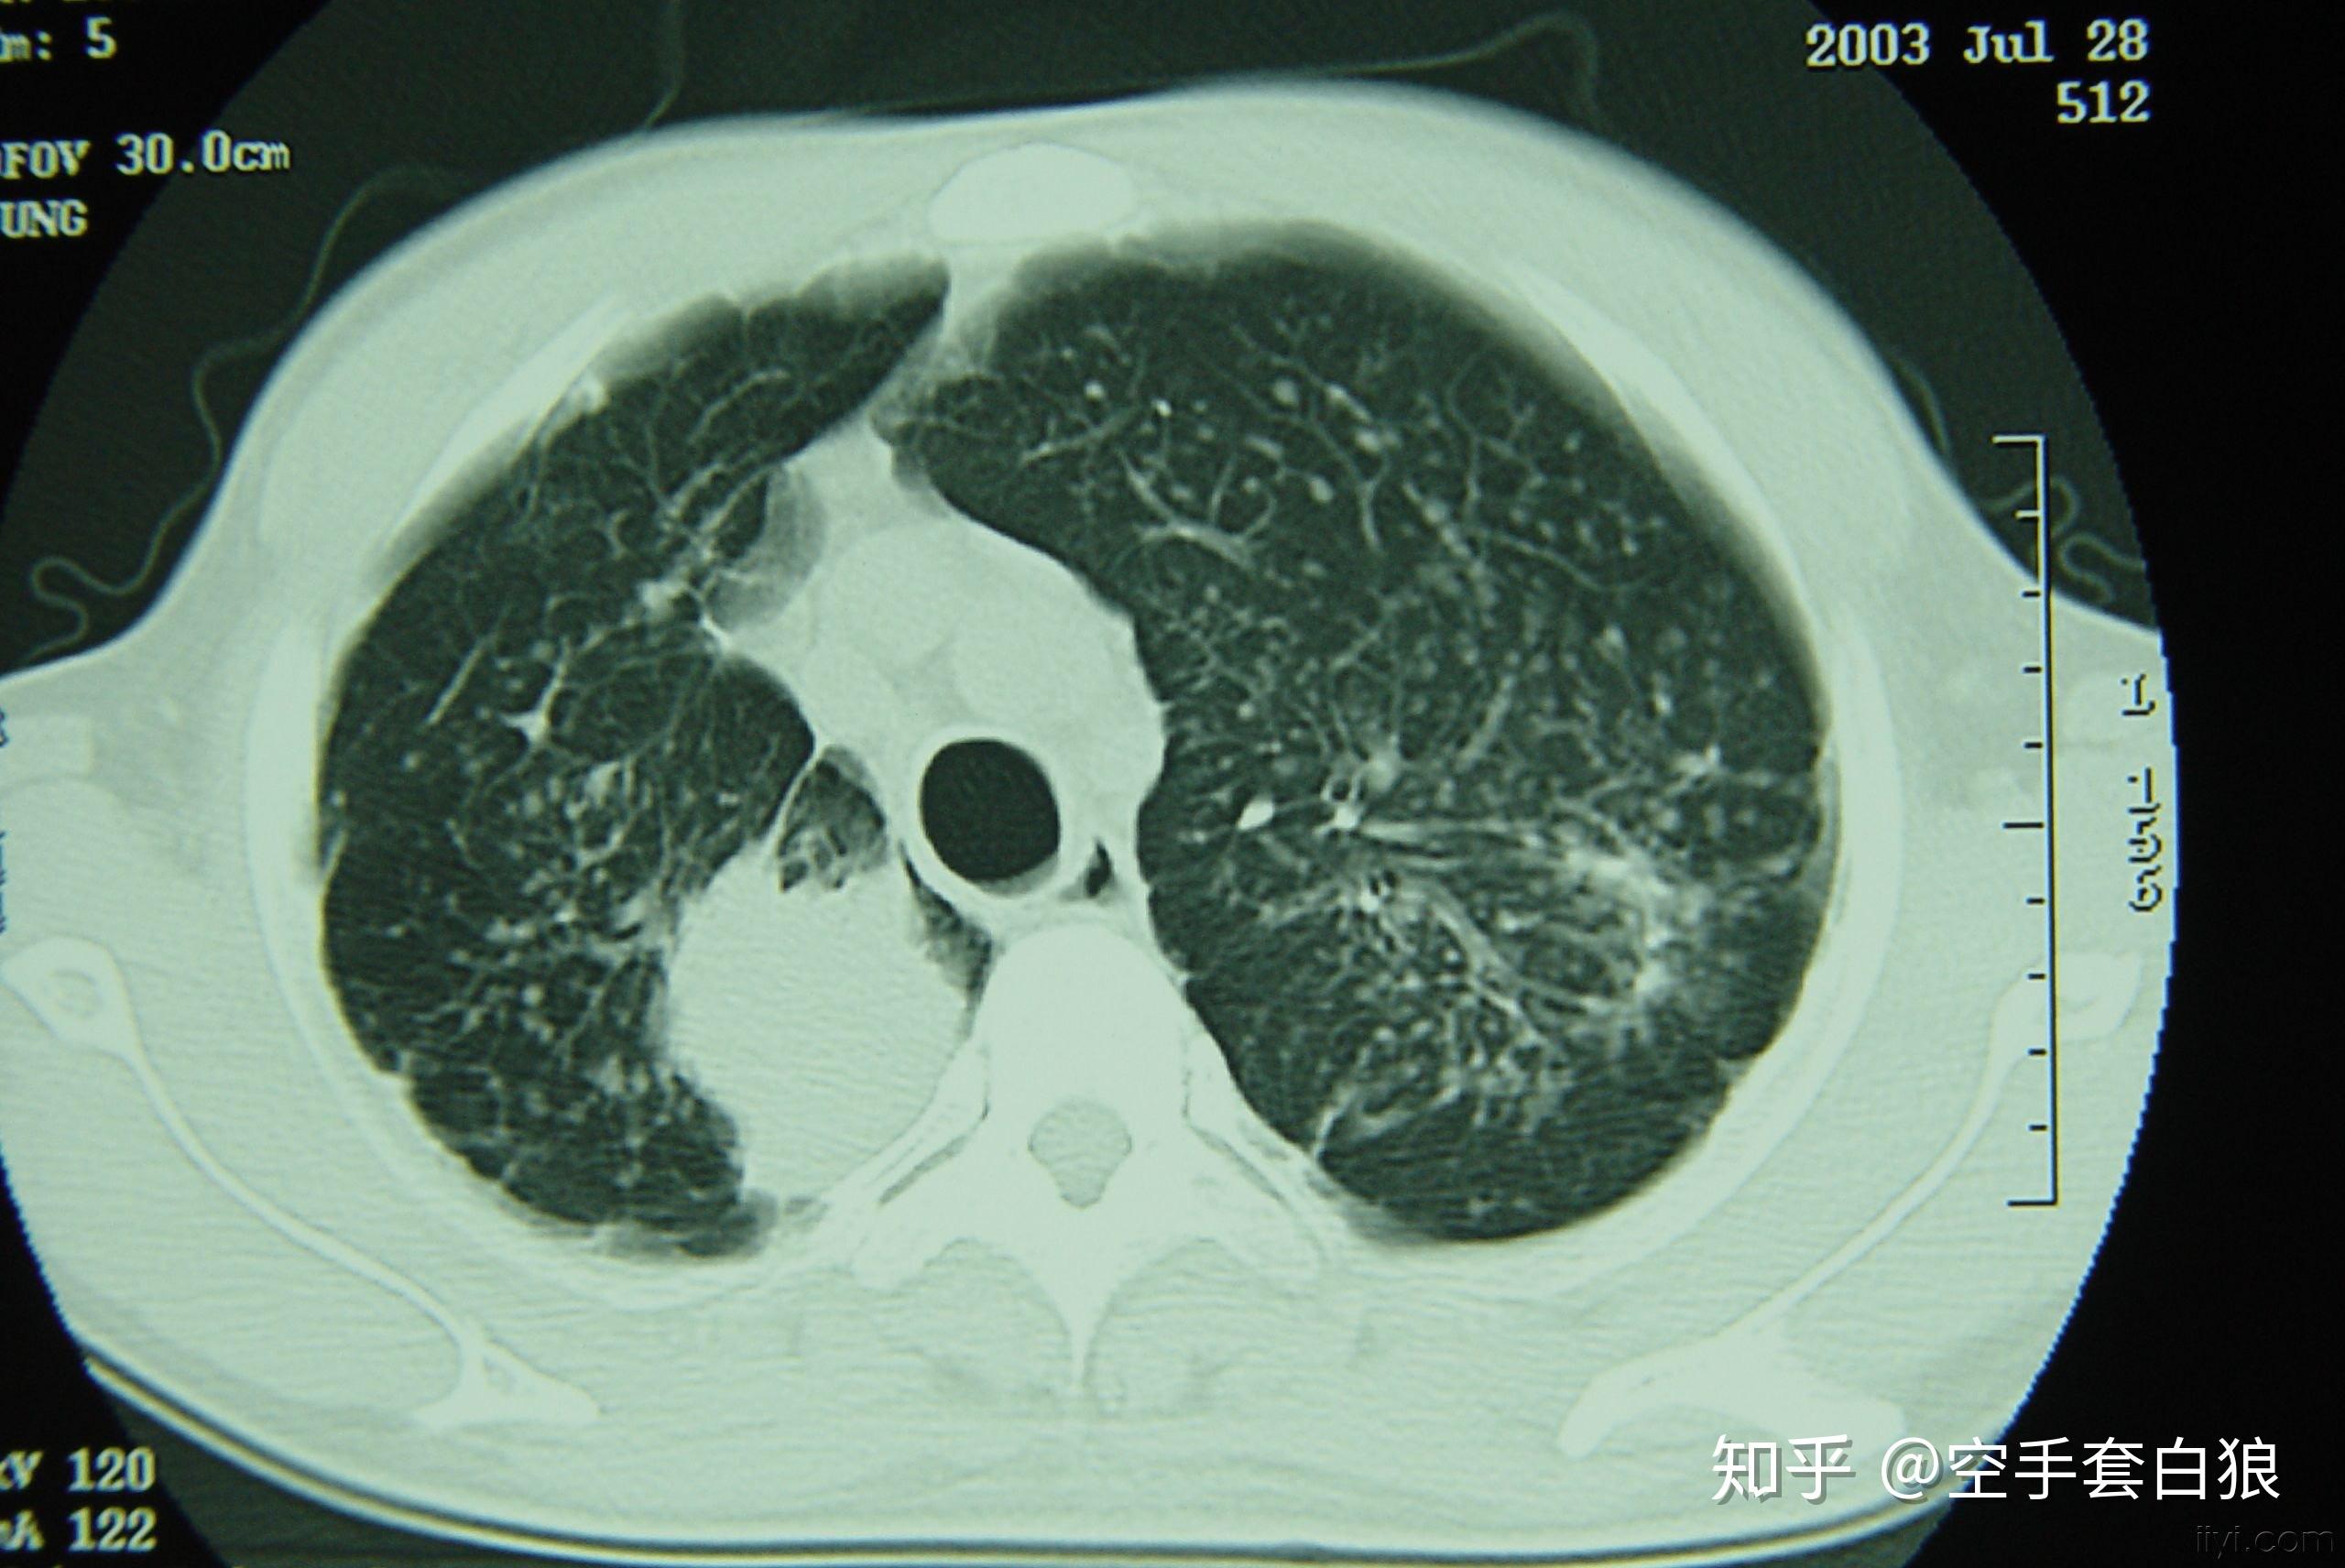

双肺纤维化病灶,说明病史很长.斑片状影,说明是活动性病灶.